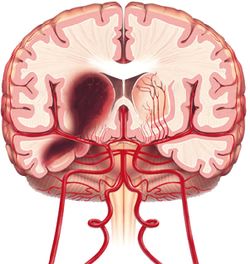

النزف الدماغي.

وفيها يحدث نزيف داخل الجمجمة يؤدي إلى أذية النسيج الدماغي وتشكل نحو 15 ـ 20% من الأمراض الوعائية الدماغية.

وهناك نوعان رئيسيان للنزيف الدماغي هما:

النزف الدماغي «تمزق شريان صغير داخل الدماغ يؤدي إلى خروج الدم من الوعاء إلى النسيج الدماغي».

1ـ النزيف الدماغي (أو داخل الدماغ) intracerebral hemorrhage: يؤلف نحو 10% من الأمراض الوعائية الدماغية. وفيه يحدث نزيف داخل النسيج الدماغي، مما قد يسبب خطورة كبيرة على الحياة نتيجة انضغاط المراكز الحيوية في الدماغ (كتلك المسؤولة عن التنفس).